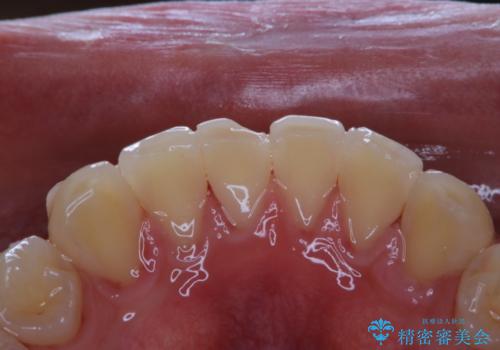

インビザラインでの矯正治療でアタッチメントset前のPMTC